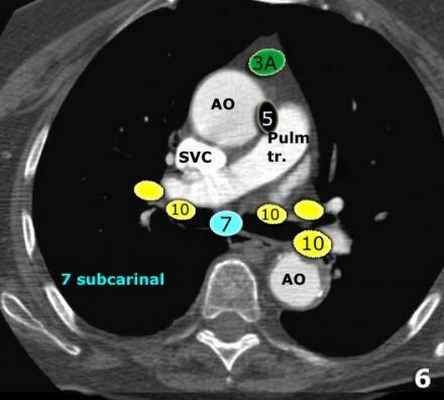

В этой статье представлены иллюстрации и КТ-изображения для лучшего понимания этой классификации.

7. Подкаринальные лимфатические узлы.

8. Параэзофагеальные лимфатические узлы. Лимфатические узлы ниже уровня карины.

9. Узлы легочной связки. Лежат в пределах легочной связки.

Корневые, долевые и (суб) сегментарные лимфатические узлы 10-14

Все эти группы относятся к N1 лимфатическим узлам.

Узлы корня легкого располагаются вдоль главного бронха и сосудов корня легкого. Справа они распространяются от нижнего края непарной вены до области деления на долевые бронхи, слева – от верхнего края легочной артерии.

7. Подкаринальные лимфатические узлы

Эти лимфатические узлы расположены ниже уровня бифуркации трахеи (карины), но не относятся к нижнедолевым бронху и артерии. Справа они располагаются каудальнее нижней стенки промежуточного бронха. Слева они располагаются каудальнее верхней стенки нижнедолевого бронха.

Слева лимфатический узел 7 группы справа от пищевода.

10. лимфатические узлы корня легкого

Лимфатические узлы корня расположены проксимальнее долевых узлов, но дистальнее медиастинальной дупликатуры и узлов промежуточного бронха справа.

Все лимфатические узлы 10-14 групп являются N1 узлами, так как они находятся вне средостения.

Группы лимфатических узлов на аксиальных компьютерных томограммах

7. Субкаринальные лимфатические узлы.

9. Лимфатические узлы легочной связки: лежат в пределах легочной связки.

10-14 лимфатические узлы N1